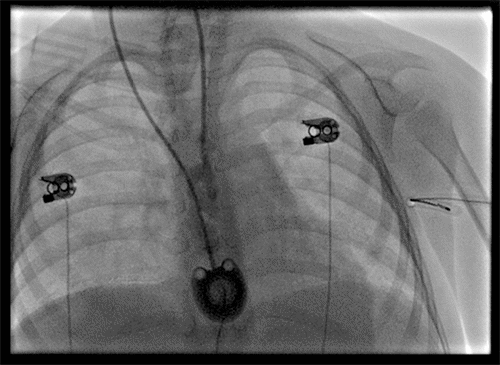

After the procedure, a chest X ray (Figure 1) confirmed the seemingly successful placement of the CVC chemo-port; the patient was transferred to the pediatrics team for postoperative monitoring. Over the next few days, the port never functioned correctly. A minimal amount of blood was able to be aspirated from the port. While it seemed to flush well, the patient would complain of severe pain when normal saline flush was injected through the port. The pain was described as being all over her body. She could not be distracted from the pain, which reportedly stopped as soon as the flush was stopped. Although no IV medication was ever administered through the port, injection of TPA was performed through the port due to a concern of sluggish blood draw from the port, which did not improve with a blood draw. Due to concern for a malpositioned port, interventional radiology was consulted and performed a port contrast study (Figure 2 and Figure 3) which revealed that the catheter was located in the epidural space, which was confirmed by a CT scan (Figure 4). The port was immediately removed while the patient was sedated in the radiology suite.

Figure 2. Beginning of Port Study. Published with Permission

Beginning of Port Study